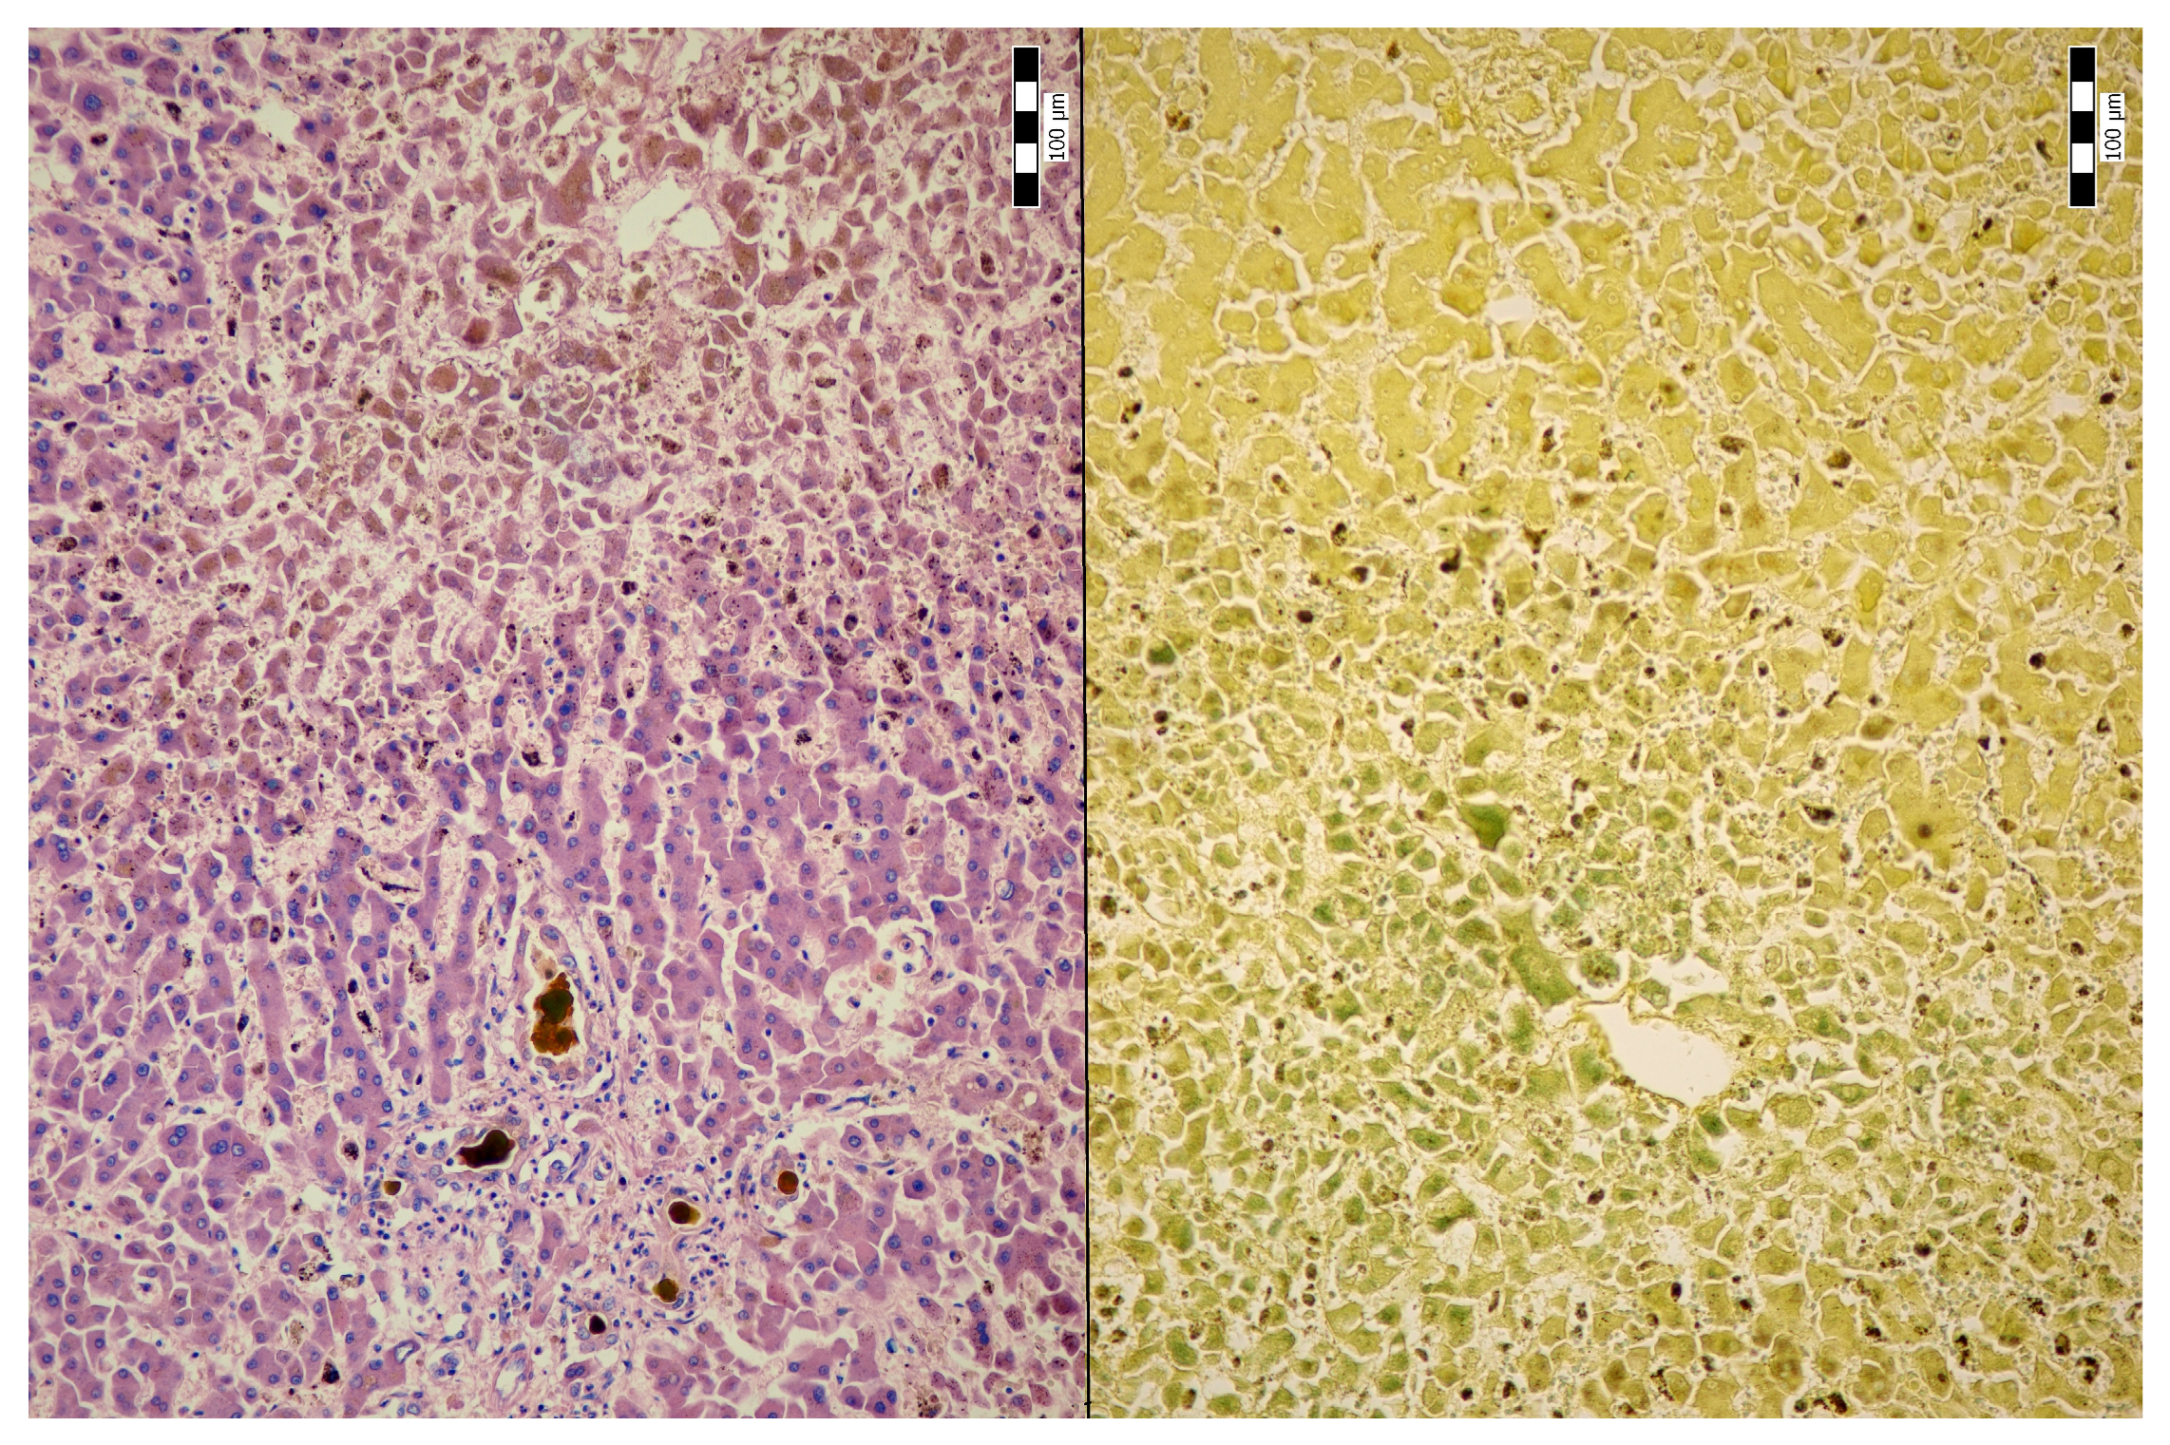

2. Case Description